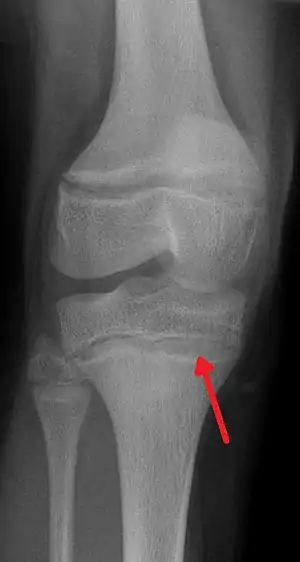

| An X ray demonstrating the characteristic finding of lead poisoning in humans—dense metaphyseal lines. | |

Exposure to lead can occur by contaminated air, water, dust, food, or consumer products.[2] Children are at greater risk as they are more likely to put objects in their mouth such as those that contain lead paint and absorb a greater proportion of the lead that they eat.[2] Exposure at work is a common cause of lead poisoning in adults with certain occupations at particular risk.[7] Diagnosis is typically by measurement of the blood lead level.[2] The Centers for Disease Control (US) has set the upper limit for blood lead for adults at 10 µg/dl (10 µg/100 g) and for children at 5 µg/dl.[8][9] Elevated lead may also be detected by changes in red blood cells or dense lines in the bones of children as seen on X-ray.[4]

Blood lead levels are an indicator mainly of recent or current lead exposure, not of total body burden.[181] Lead in bones can be measured noninvasively by X-ray fluorescence; this may be the best measure of cumulative exposure and total body burden.[33] However this method is not widely available and is mainly used for research rather than routine diagnosis.[95] Another radiographic sign of elevated lead levels is the presence of radiodense lines called lead lines at the metaphysis in the long bones of growing children, especially around the knees.[182] These lead lines, caused by increased calcification due to disrupted metabolism in the growing bones, become wider as the duration of lead exposure increases.[182] X-rays may also reveal lead-containing foreign materials such as paint chips in the gastrointestinal tract.[22][182]